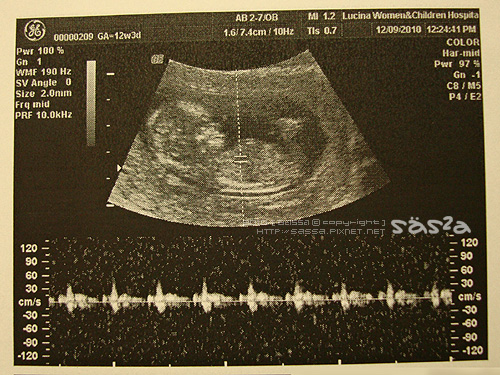

今天又見到了我的小麻醬。

今天的小麻醬一樣是非常活潑,連醫生都忍不住又稱讚小麻醬怎麼這麼興奮,當我們一邊照超音一邊拉天說笑的時候,為娘我大笑,小麻醬動的更是厲害。嘖嘖嘖!相較於哥哥的產檢,幾乎都給我在睡覺中!

第二胎了我還是很難想像,眼前螢幕中這個小形狀才5點多公分?人體真是奧妙!醫生仔細丈量小麻醬的各部位,我們清楚的看見小麻醬的四肢,看的正開心哩!醫生就被護士call去接生,吼優!為娘我還沒看夠耶!當醫生照到小屁屁的時候,我們似乎都看見了非常明顯的部位,醫生說『我沒說喔!我沒說喔!還不確定!』我試圖讓醫生告訴我『我不care耶!告訴我啦!』醫生說『我也不care耶!』唉!只好回醫生你當然不care就結束這個話題。臭醫生,我們都這麼熟惹XD

醫生說小麻醬發展的很不錯便火速去接生了,祝那位產婦平安順產!

[12w]似乎發現你的性別